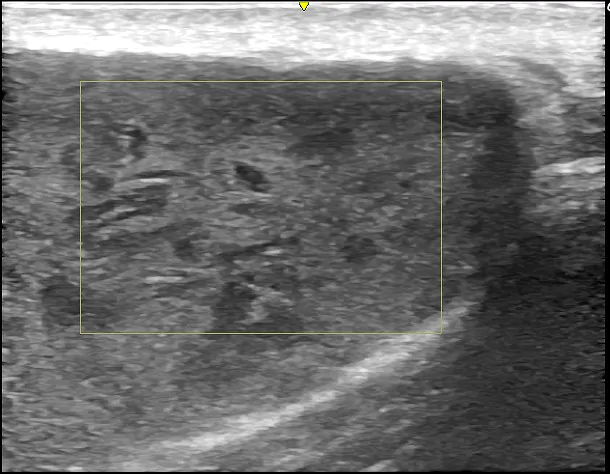

徐々に皮下腫瘍が大きくなったため、当院を受診されました。左肩に120mm大の巨大な皮下腫瘍があり、超音波検査の結果、典型的な粉瘤と診断されました。

術前